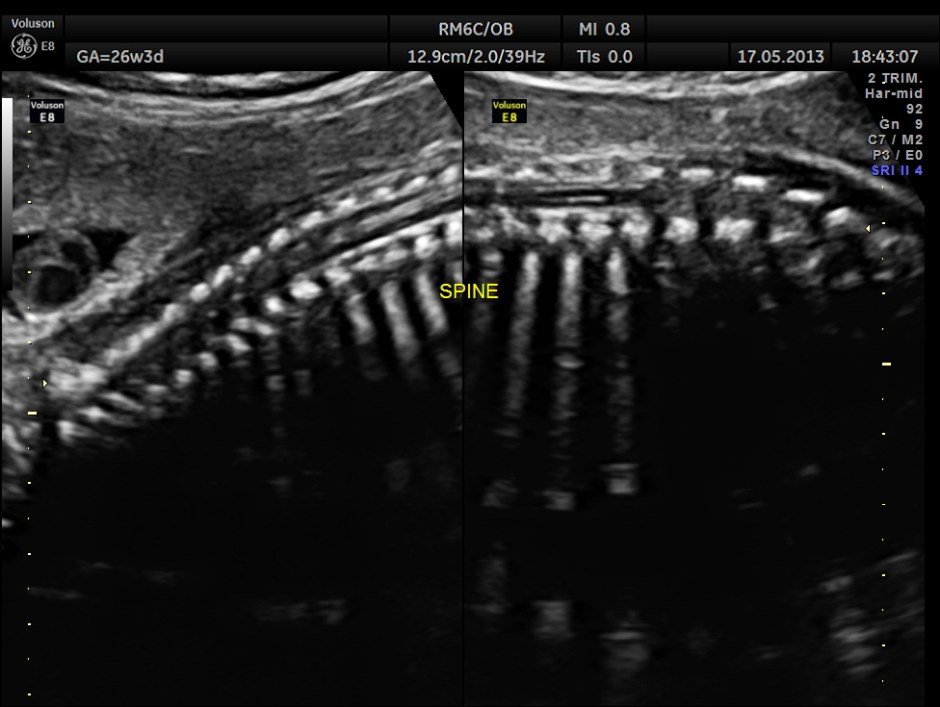

The following images show the spine.